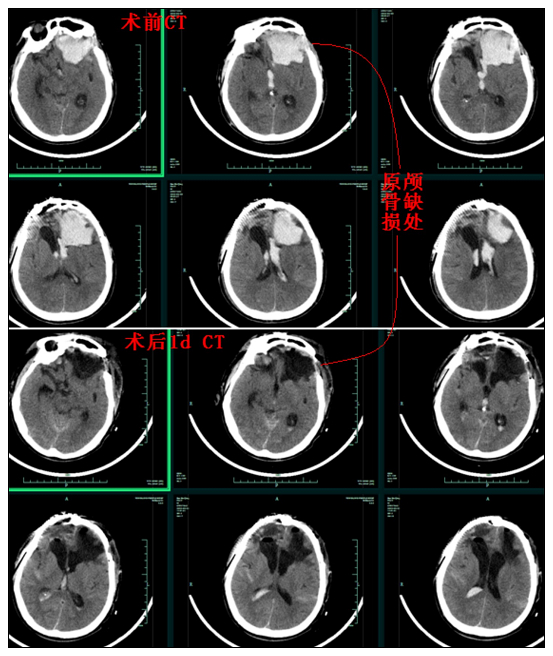

患者为63岁男性,头部外伤6小时入院,来院时神志朦胧,急诊CT提示:双额叶软化灶及手术迹,左额脑挫裂伤伴血肿38ml,蛛网膜下腔出血。

因为患者数年前的一次重度颅脑外伤和双侧开颅手术史,家属对开颅手术心有余悸,入院后要求保守治疗观察。但是,经积极保守治疗后,患者意识障碍逐渐加重,复查CT示:左额脑内血肿增加明显,量约70ml余,并破入脑室伴第三、四室脑室铸型,急性脑积水形成。性命垂危,非手术不可!医生与家属积极沟通,详细解释首选微创手术方式,以开颅手术为补救方案,家属表示理解并最终同意手术。

急诊行神经内镜下左侧脑内及脑室内血肿清除术,术中医生巧妙利用部分原切口,仅利用原有的额骨约2cm*2cm大小缺损,神经内镜下微创清除脑内和脑室内血肿,术中失血仅50ml。术后动态复查CT示:颅内血肿基本清除,颅内结构恢复良好,效果满意。术后经过积极的对症治疗,患者顺利康复出院。经回访,患者现一般情况良好,四肢活动正常,生活可自理。